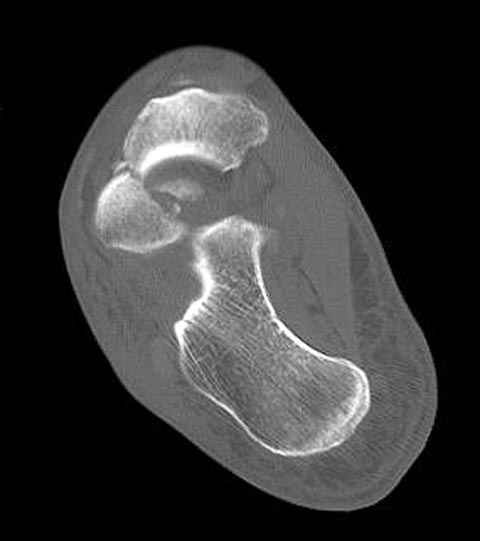

Уважаемые участники русского Ортофорума, поздравляю всех со всеми прошедшими праздниками: Новым годом, Рождеством, Hanukkah, Kwanzaa, желаю участникам всего наилучшего и здоровья.Повреждение таранной кости.Больной 81г автоавария, повреждение таранной кости, здесь снимки. Какие рекомендации?Djoldas Kuldjanov, MDDepartment of Orthopedic SurgerySt. Louis University Medical Center

Вдогонку по поводу перелома таранной кости, больная 81, не страдает диабетом, перелом закрытый, в первый же день поступления ограничились временным наружным фиксатором (как на снимке).

Планировалась открытая фиксация после спадения отека, но больная пожелала лечиться по месту жительству в другом штате..

За пару недель насчитал 5 больных с переломом таранной кости, из них двое с двусторонним повреждением.

Из-за отека на стопе тактика лечения у всех была

одинаковая: временная наружная фиксация до спадения отека, при изолированных переломах они выписывались домой и через дней 7 госпитализировались на оперативное лечение.

Примеры на снимке...